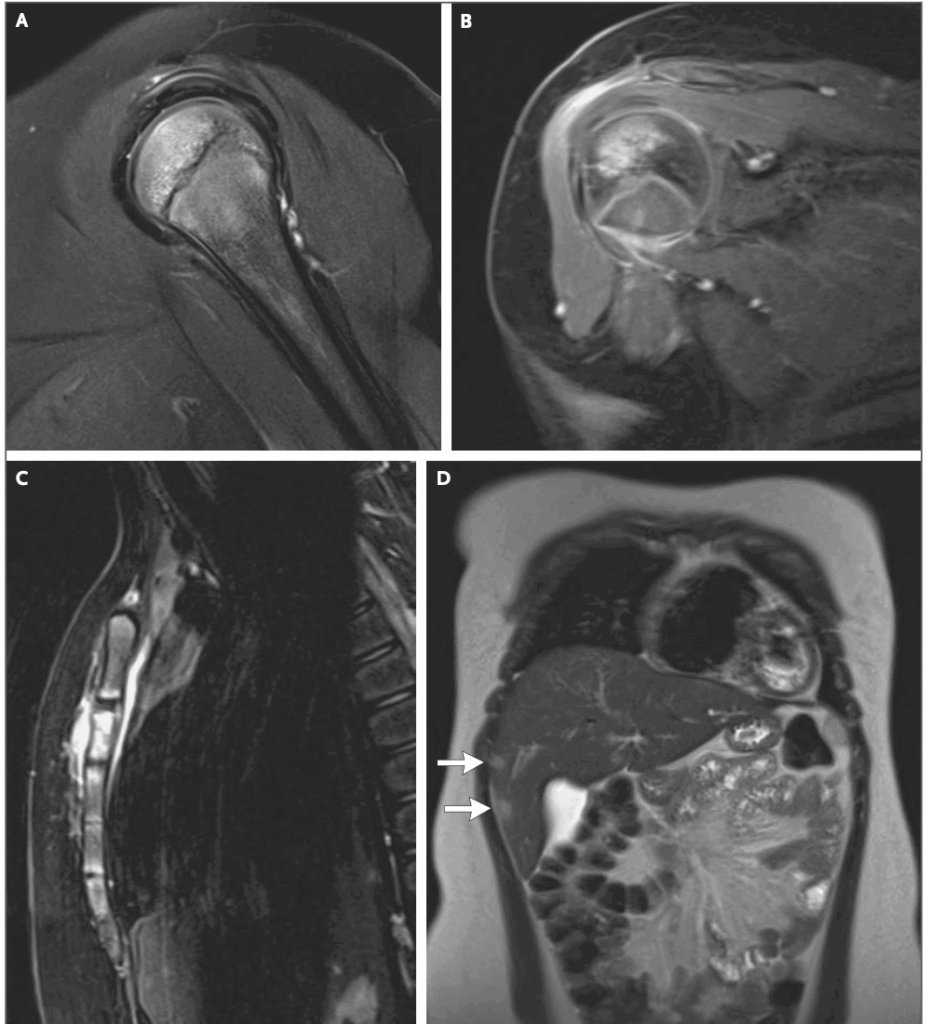

11歳女児の7日程度の経過で認めた胸痛、多発骨病変(胸骨、右上腕骨頭)、多発肝病変の症例です。既往はアトピー性皮膚炎、MRSA皮膚感染症があり、子猫を飼い始めたという生活歴があったようです。血液検査は炎症反応以外はパッとしないという感じです。下に論文内の画像所見を貼っています。

全身疾患となった場合、バルトネラは肝臓、骨、眼、中枢疾患などに播種性病変を形成し、不明熱の原因疾患とされる。下肢の骨や脊椎病変が多いが、あらゆる腸管骨や胸骨も病変を形成しうる。肝臓や脾臓に多発微小膿瘍を形成することがあり、本症例と合致する。